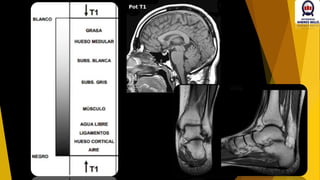

Grasa  HIPERINTENSO

Sust. Blanca HIPERINTENSO

Sust- gris  iSOINTENSO

LCR (Agua) HIPOINTENSO

LCR (Agua)  HIPERINTENSO

Sust. Gris HIPERINTENSO

Sust- Blanca  HIPOINTENSO

Sust- Blanca  ISOINTENSO

Aire  HIPOINTENSO